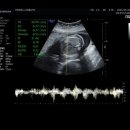

29주 후기 글입니다! (모든 아가들 건강하자,,,) 이날 증상이 배아픔 아랫배통증 심했어요 근데 배 아픔이 평소랑 다르게 콕콕 쑤신 데야 하나? 배도 너무...가는 게 맞다! 츄츄 이상 없다는 말 듣고 와야겠다 싶어서 부랴부랴 미즈웰산부인과 전화해서 배아픔 아랫배통증 증상 말씀드리고 바로 택시 타고...

방방곳곳 떠나는 일상 여행 ✈️(2025-11-06 14:14:00)